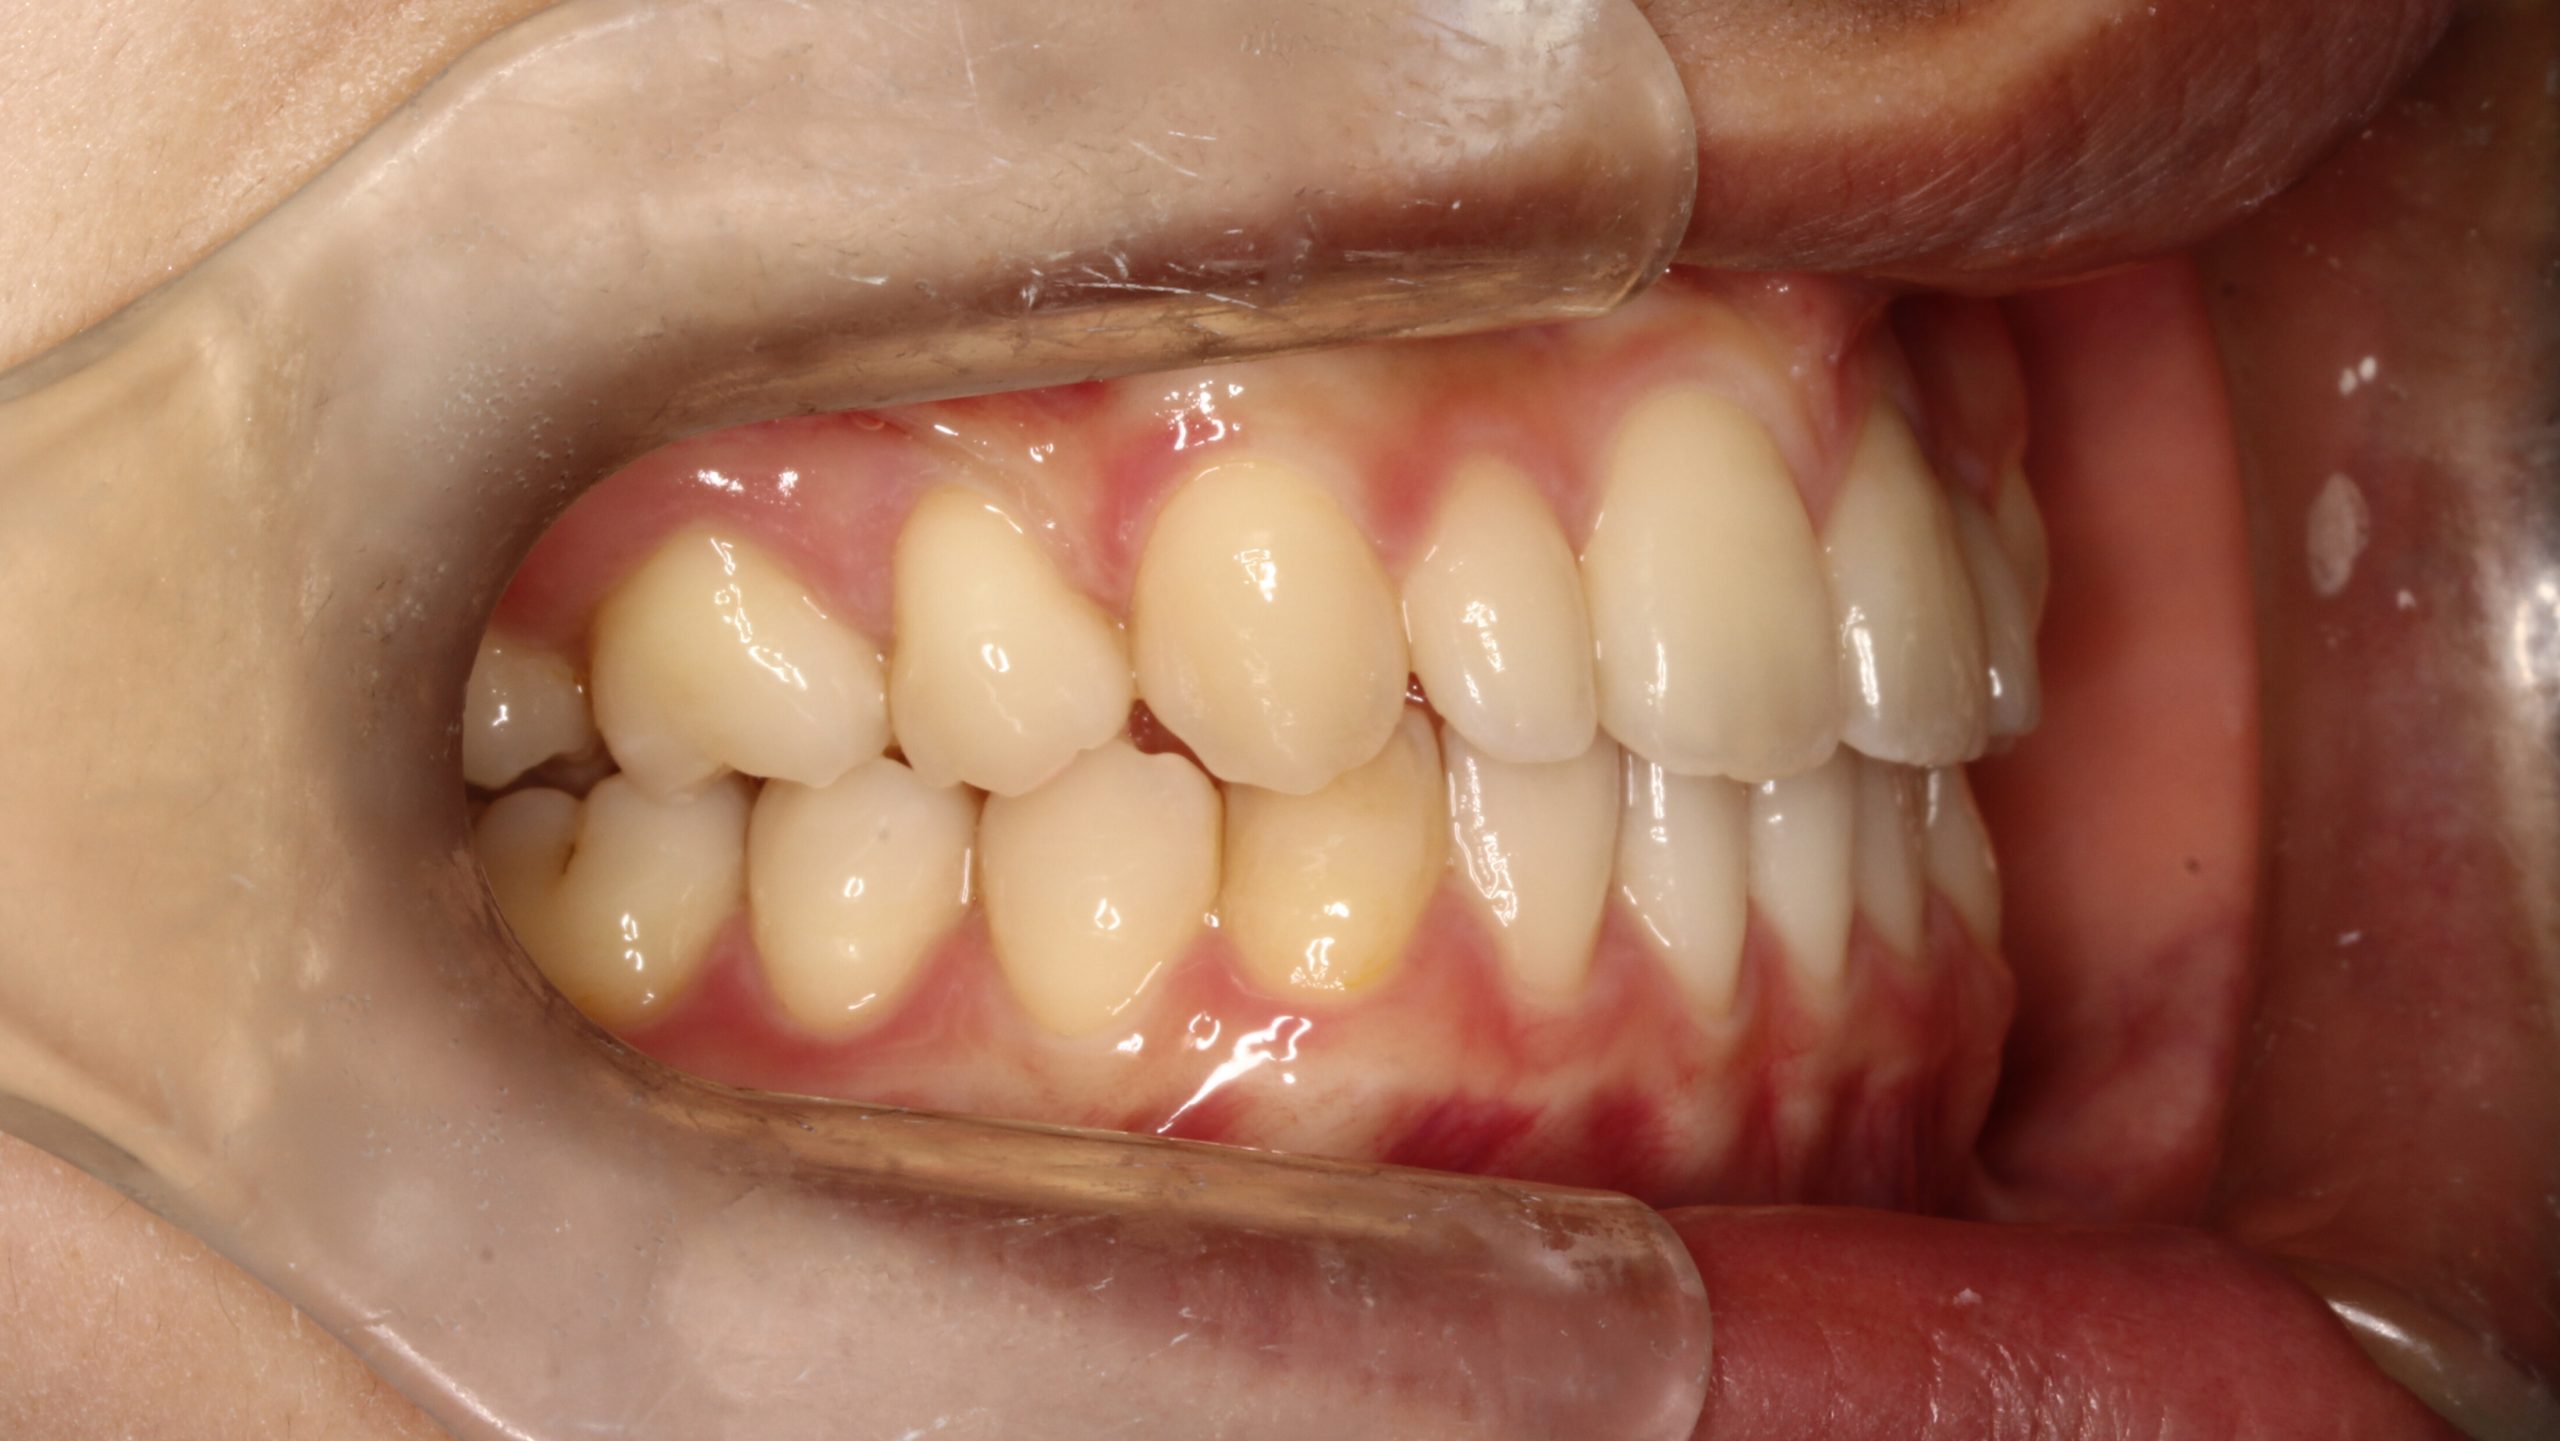

上の歯が出ている、嚙み合わせが悪い(治療期間:2年4か月/通院32回)

Before